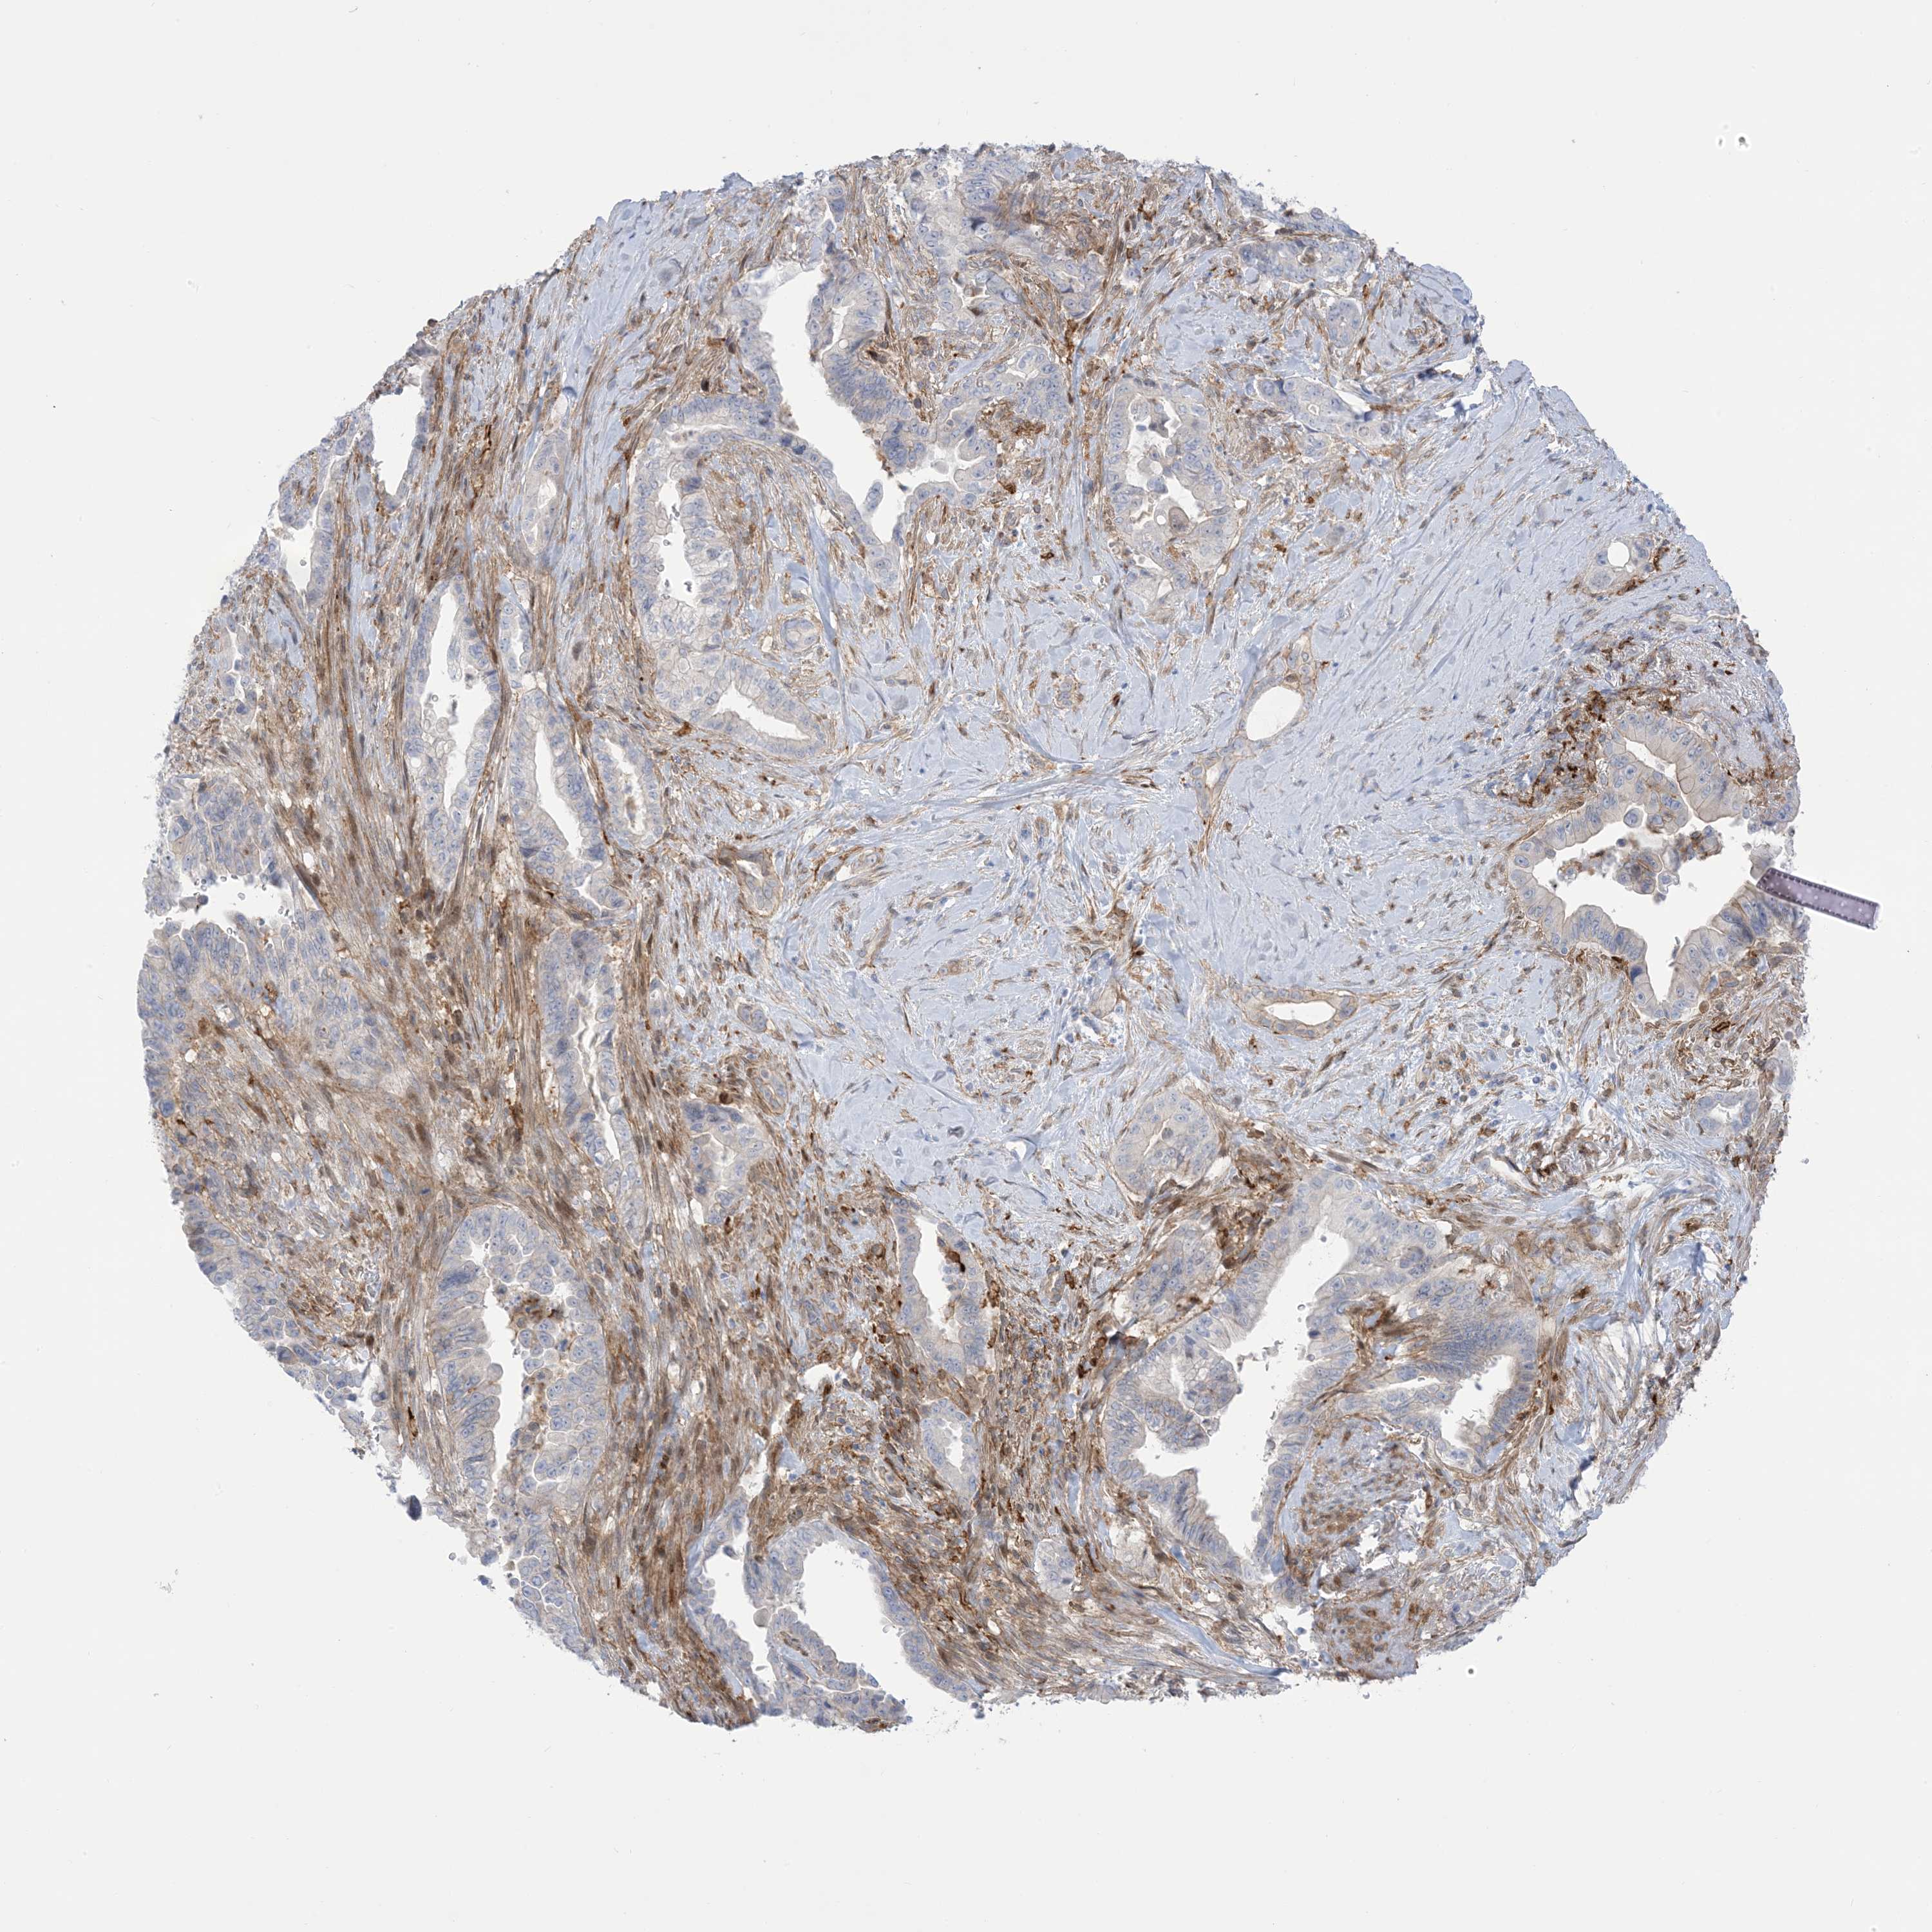

PANCREATIC CANCER - Protein expressioni

A mouse-over function shows sample information and annotation data. Click on an image to view it in a full screen mode. Samples can be filtered based on level of antibody staining by selecting one or several of the following categories: high, medium, low and not detected. The assay and annotation is described here.

Note that samples used for immunohistochemistry by the Human Protein Atlas do not correspond to samples in the TCGA dataset.

Antibody stainingi

Antibody staining in the annotated cell types in the current human tissue is reported as not detected, low, medium, or high, based on conventional immunohistochemistry profiling in selected tissues. This score is based on the combination of the staining intensity and fraction of stained cells.

Each image is clickable and will lead to virtual microscopy that enables deeper exploration of all samples and also displays staining intensity scores, fraction scores and subcellular localization as well as patient and tissue information for each sample.

Antibody HPA032024

Antibody HPA032025

Staining

High

Medium

Low

Not detected

Intensity

Strong

Moderate

Weak

Negative

Quantity

>75%

75%-25%

<25%

None

Location

Nuclear

Cytoplasmic/membranous

Cytoplasmic/membranous,nuclear

Adenocarcinoma, NOS